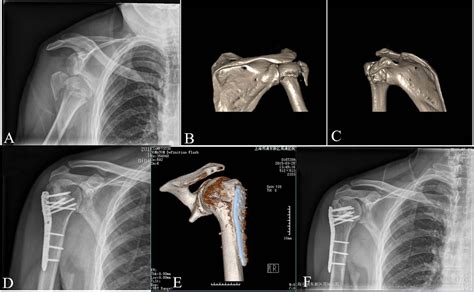

When a physician suspects a humeral neck fracture, the diagnostic journey typically begins with a physical examination to check for nerve function and blood flow. Imaging is the gold standard for confirmation. X-rays are usually the first step, providing clear images of the bone fragments. In more complex cases where fragments are not clearly defined, a CT scan may be ordered to assess the degree of displacement and help the surgical team plan the best course of action.

If the bone fragments are significantly displaced or the fracture is unstable, surgical intervention becomes necessary. This might involve:

• Open Reduction and Internal Fixation (ORIF): Surgeons use metal plates, screws, or pins to realign the bone and hold it in place while it heals.

• Hemiarthroplasty: In severe cases, especially among elderly patients with poor bone quality, replacing the head of the humerus with a metal prosthesis may be the most viable option.

• Reverse Total Shoulder Arthroplasty: Often used for complex fractures in older populations to restore better function than a standard replacement.